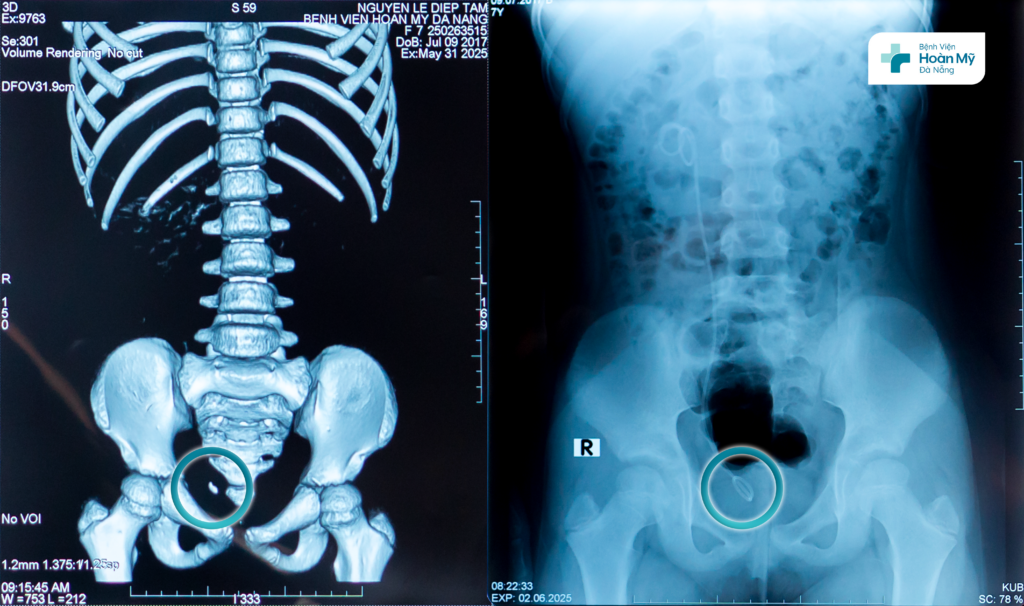

Bệnh nhi sạch sỏi niệu quản sau điều trị nội soi tán sỏi ngược dòng

2 ngày sau phẫu thuật, trẻ đã ổn định, hết đau, dòng tiểu thông thoáng, kiểm tra trên phim thấy sạch sỏi và có thể xuất viện về nhà.